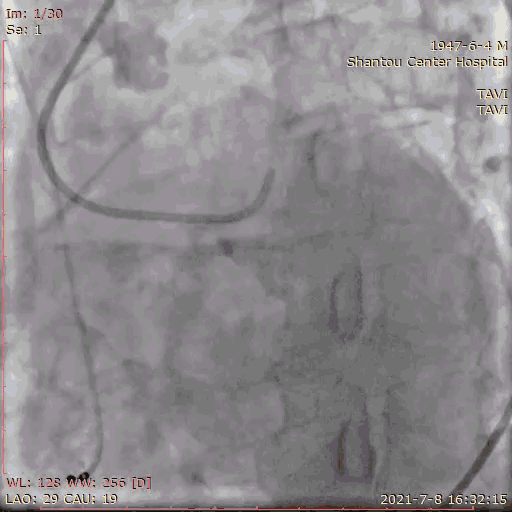

手术流程

术前怀疑冠脉有狭窄,一站式冠脉造影检查,狭窄程度无需行PCI。

冠脉造影

左右冠通畅,存在一定反流,有一定耐受能力,球扩时,循环崩溃风险较小。双侧瓣叶活动度高。

主动脉根部造影

180bpm起搏后打球囊,造影,撤球囊,停起搏;25球囊预扩后有略微漏,冠脉通畅,选择32瓣膜。

球囊预扩张

输送系统定位,标准位置释放

120bpm起搏

轻微反流,压差降低